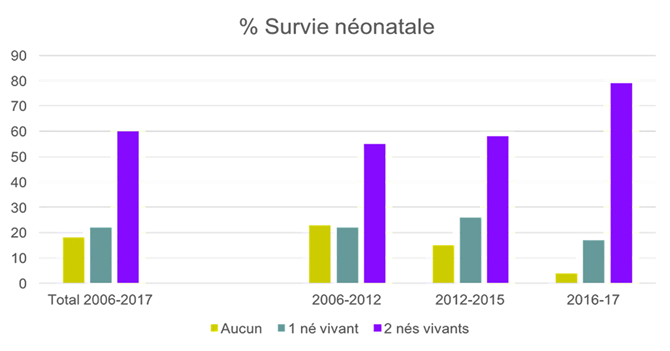

Données statistiques CHU Sainte-Justine (2006-2016)

Depuis 10 ans, plus de 150 procédures de fœtoscopie-laser pour STT ont été réalisées au CHU Sainte-Justine.

Le taux de survie néonatale pour au moins un jumeau est de 81%, avec survie des deux jumeaux dans 60% des cas. Les résultats se sont progressivement améliorés au fil des années (voir graphique) et sont équivalents à ceux des principales équipes au monde.

Plusieurs publications reliées au laser et STT faites par notre équipe (Prenatal Diagnosis 2016 et 2018; Fetal Diagnosis and Therapy 2017; Journal of Perinatology 2018)

Depuis 10 ans, plus de 150 procédures de fœtoscopie-laser pour STT ont été réalisées au CHU Ste-Justine.

Le taux de survie néonatale pour au moins un jumeau est de 81%, avec survie des deux jumeaux dans 60% des cas. Les résultats se sont progressivement améliorés au fil des années (voir graphique) et sont équivalents à ceux des principales équipes au monde.

Plusieurs publications reliées au laser et STT faites par notre équipe (Prenatal Diagnosis 2016 et 2018; Fetal Diagnosis and Therapy 2017; Journal of Perinatology 2018)